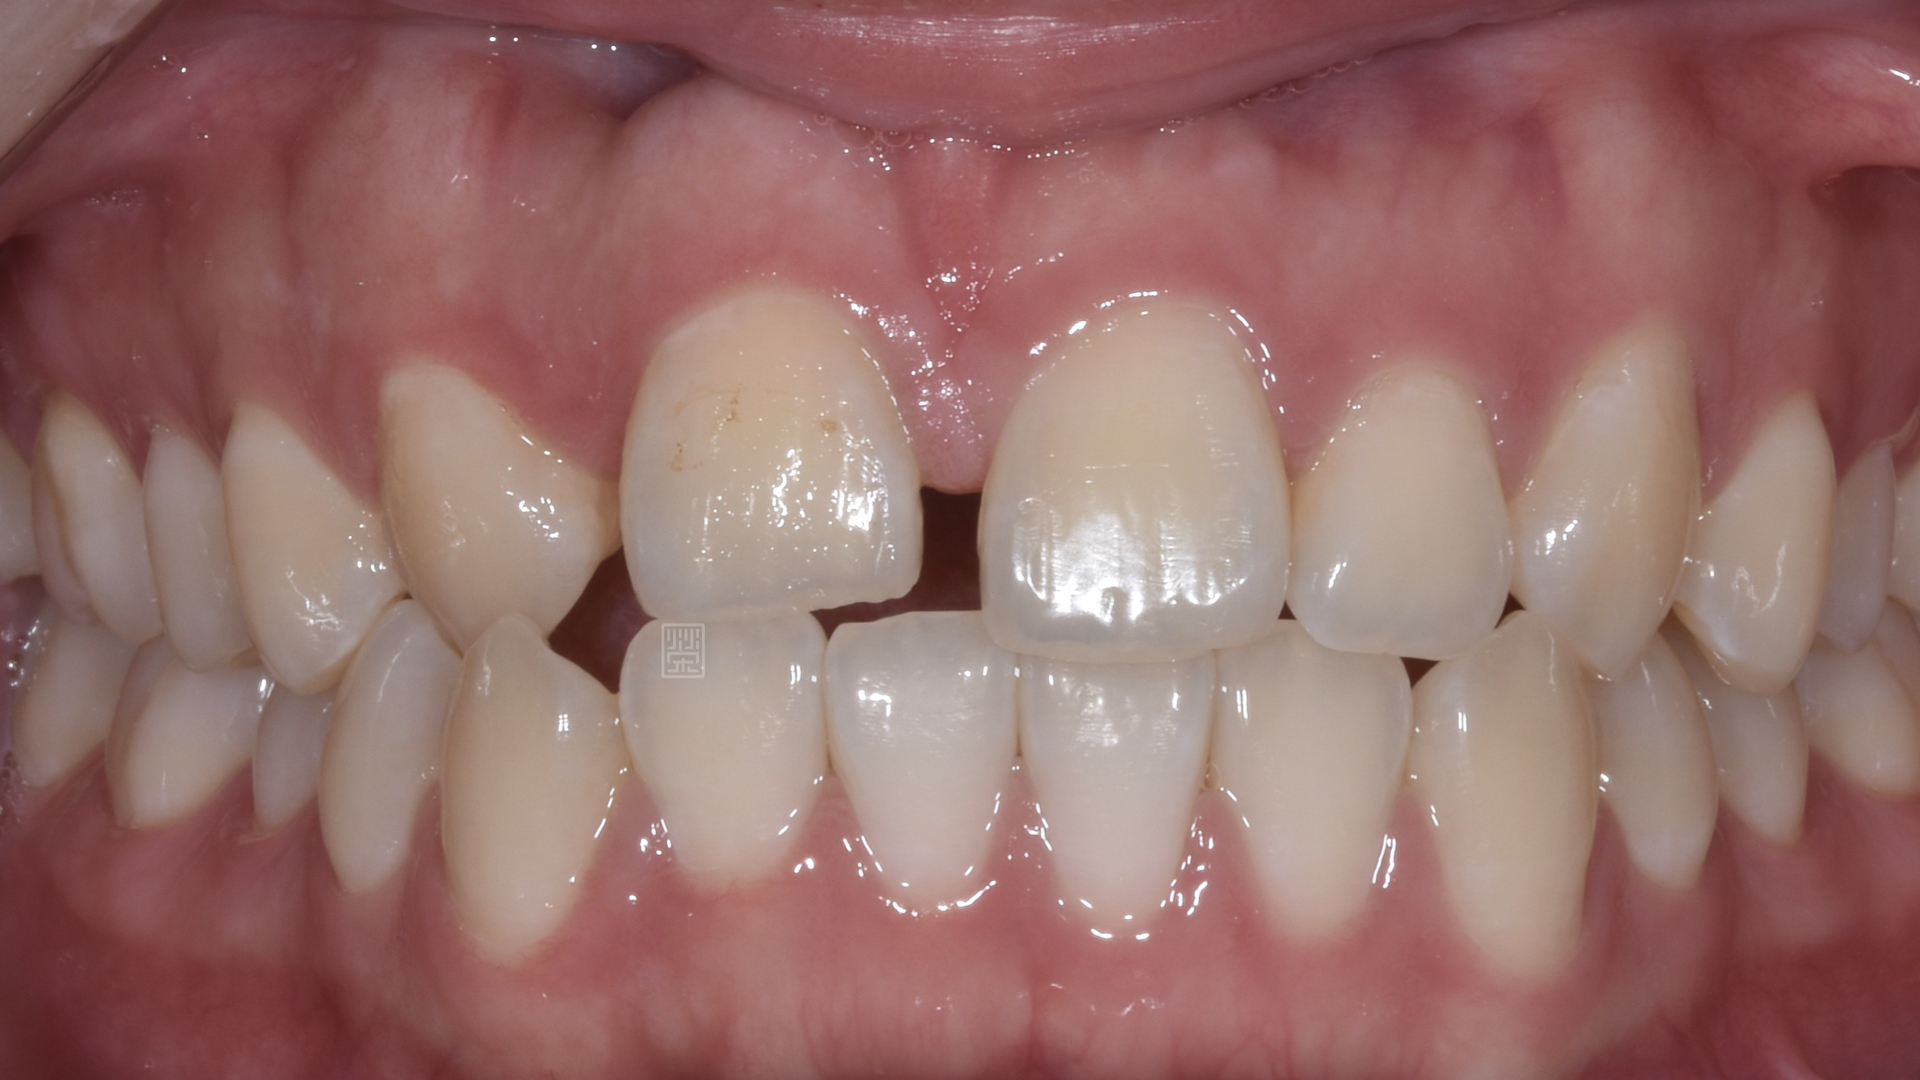

由於門牙本身偏短,藉由微笑分析,決定由牙冠增長術與改變牙齒長度讓門牙達到更好的比例與對稱性,加上側門牙植牙牙齦的調整,並且將右側犬齒用全瓷冠恢復犬齒導引,達到保護性咬合,對未來咬合性穩定性更有幫助。

全瓷冠位置、牙齦線位置評估